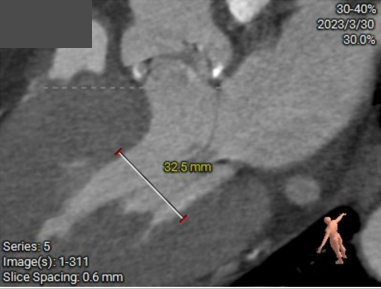

三叶瓣,瓣环偏大,右无瓣叶钙化重;LVOT直径小于瓣环直径,呈漏斗形;窦部直径可,STJ及升主直径偏小,双冠脉高度可;主动脉根部角度约39°;室间隔及室壁增厚,LV偏小。

环上钙化分布较为均匀,限制区高度4-12mm,开口最受限处位于环上8mm,预估瓣膜锚定良好。